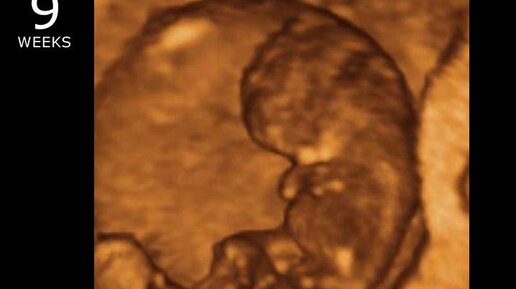

8-9 недель беременности и самая частая ошибка врача УЗИ

Здравствуйте. Меня зовут Марина Багдасарян, я врач ультразвуковой диагностики, специализируюсь в области пренатальной диагностики, также являюсь врачом акушером-гинекологом. В этой статье я расскажу про развитие малыша , а также про самые частые ошибки врача ультразвуковой диагностики и их последствия.

Итак, наш малыш уже стал побольше, Он ростом уже 20 -30 мм и весом до 5-6грамм.

На этих неделях также происходит активное развитие органов и систем плода , продолжает развиваться головной мозг...